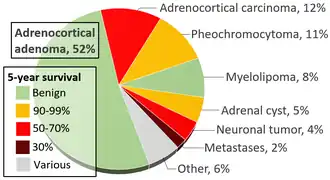

- ^ Data and references for pie chart are located at file description page in Wikimedia Commons.